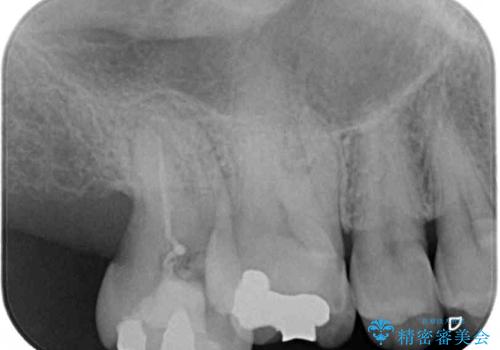

上顎の奥歯は、左右ともに外側に転位しており、特に右上はむし歯の範囲が広く、根管治療も必要な状態でした。

左下の奥歯は状態が非常に悪く、保存は困難と判断されたため、インプラントによる補綴治療が必要でした。

上顎左右の歯をアンカースクリューを用いた部分矯正により位置を修正し、オールセラミッククラウンにて補綴治療を行うこととしました。